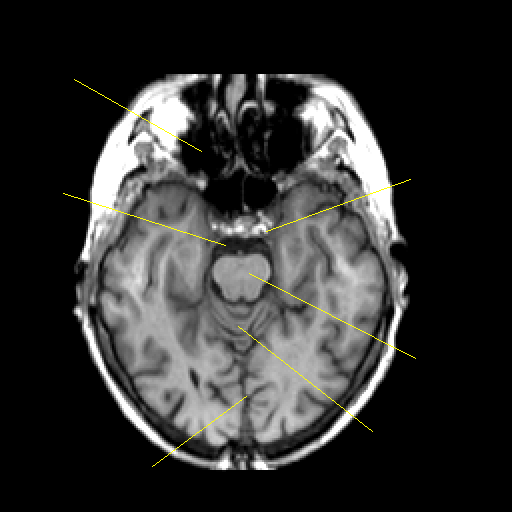

T1-weighted structural MR: Slice 19

Slice 19

Pointers

Labeled